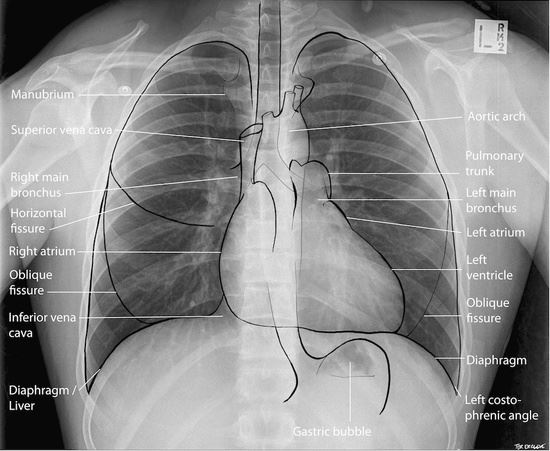

Bản tiếng viết: Chest Xray for Medical Student Đăng vào Tháng 9 26, 2017Tháng 6 28, 2020 bởi quản trị viên Tải TẠI ĐÂY Ebook Cơ chế triệu chứng học